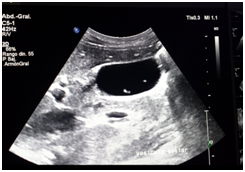

Male patient of 37years of age , white race, resident in Habana del Este municipality of Havana province, with previous health history that comes to consultation for presenting prolonged febrile syndrome with 56days of evolution, febrile peaks of 38‒39 degrees, accompanied by chills and decay. Urinary sepsis was determined as initial diagnosis so antimicrobial treatment was imposed for 10 days. There is no improvement in the clinical picture and the febrile symptoms persist. The patient is admitted to the hospital service of the Central Hospital in Havana. On physical examination, painful abdomen on palpation in the right hypochondrium and epigastrium without other alterations Laboratory tests are performed or presenting Haemoglobin: 12gl, Leucogram which yields an Eosonophilia of 66% and an Erythrosedimentation: 67. Serial blood cultures and urine cultures they were negative. Likewise, the serology was negative. Within imaging studies abdominal ultrasound reporting hepatomegaly that exceeds be 2 cm costal margin with the presence of a hypo echoic image with nodular, peripheral tendency without flow Doppler level right lobe study (Figure 1) interpreting c indicated omo pyogenic liver abscess therefore imposes treatment with antimicrobial therapy (Metronidazol EV) (Figure 1). Ultrasound: nodular, hypoechoechoic, peripheral, non‒vascularised image at the level of the right lobe of the liver clinically the patient improved his general condition, but he kept the febrile syndrome accompanied by diffuse abdominal pain. By keeping the same ultrasound image last month of treatment study it was conducted by T omografía who reported abdominal the presence of density areas of irregular appearance, in the right lobe of the liver in segments VII and VIII and endovenous study showed lesions with poor contrast capitation both Portal and late phase (Figure 2). Computed tomography with intravenous contrast: hypo dense areas of irregular appearance at the level of segments VII and VIII of the liver with poor contrast uptake Ultrasound images suggested the diagnosis of parasitosis Fasciola hepatica but also by positron raised the differential diagnosis of Focal nodular hyperplasia at que sugi river echo directed FNA that reported cytological Negative of neoplastic cells and inflammatory infiltrate with abundant eosinophils. Given this possible diagnosis, endoscopy was performed, which reported alkaline pangastropathy with a duodenal swab for negative parasitological study. Conical crown was made on several occasions resulting negative and biliary drainage was indicated to be not useful for diagnosis. In view of Clinical and Imaging suspicion of Fasciola hepatica, it was decided to perform a weekly evaluative ultrasound for 4 more weeks, observing at the end of the fourth week echogenic images, elongated with movements inside the gallbladder and an echogenic image without acoustic shadow in the canal. Coledochus suggesting the diagnostic imaging of adult Fasciola parasites in the bile ducts (Figure 3). Evolutionary ultrasound: echogenic images, free, with movement at the level of the gallbladder. The patient was referred to the Institute of Tropical Medicine (IPK) where the diagnosis was verified, imposing treatment with a single oral dose of Triclabendazole with excellent therapeutic response.

Figure 2 Computed tomography.

Computed tomography

In Fasciolosis hepatica, it can present as nodular or tortuous lesions, with enhancement after variable contrast, although in 80% it allows its better delimitation in late phases. However, the most characteristic of these lesions is their sub capsular location, with tortuous paths that adopt a centripetal direction in the direction of intrahepatic bile ducts, whose appearance makes some authors propose it as highly suggestive of Fasciolosis (Figure 2).16–18 Hepatic capsule enhancement with contrast injection is also described, which correlates with thickening and inflammation of the capsule observed in laparoscopy. Another element to consider is the sub capsular hematoma, an infrequent complication, but one that undoubtedly requires imaging control. In relation to biliary fasciolosis, the role of CT in its diagnosis is smaller, being able to only show minimal dilation of the extra hepatic bile duct, being a non‒specific finding.17 In the patient reason for discussion, both Tomography and Ecography could be useful, the latter being the one that contributed most to the definitive diagnosis, coinciding with the findings reported in the literature according to the clinical phase of the disease.